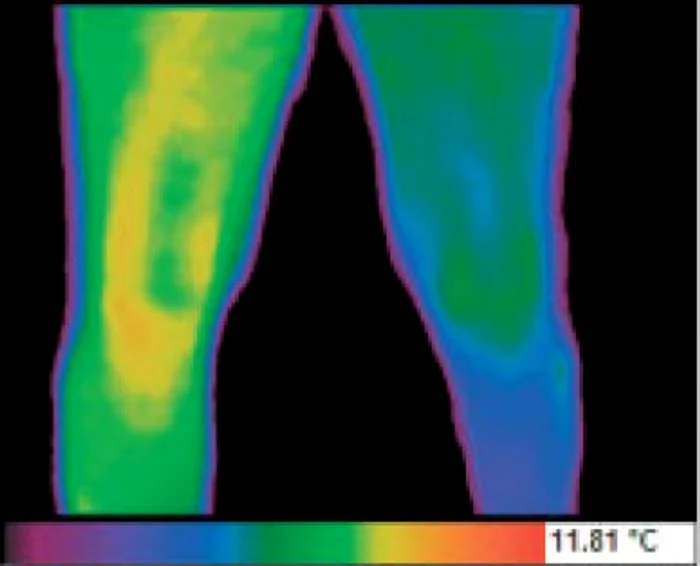

Medicul pune diagnosticul în funcţie de intensitatea şi de variaţia culorilor zonei explorate termografic.

„Culoarea verde corespunde unui ţesut sănătos, normal, culoarea galbenă (hipertermie) cu intensităţi diferite (de la galben până la roşu) corespunde zonelor cu probleme, iar culoarea albastră (hipotermie) este asociată zonelor slab vascularizate sau lipsite de vascularizaţie, care orientează către un alt diagnostic”, spune medicul Adrian Hrihor, cu competenţă în termografie.

Arteriopatia obliterantă